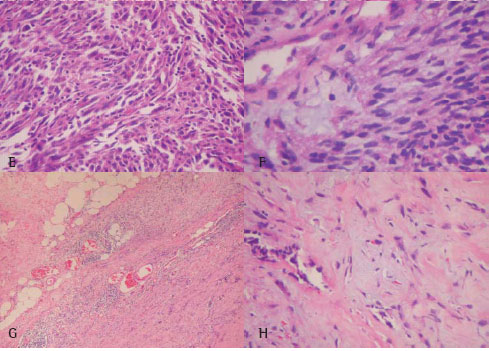

Departamento de Patologia do Hospital Pedro Ernesto (RJ). A reavaliação histológica dos subtipos foi realizada por dois patologistas de acordo com a classificação atual da Organização Mundial de Saúde. Nos casos em que a histologia revelou aspectos incomuns para mesotelioma tentou-se um diagnóstico diferencial. Duas categorias principais de diagnóstico histopatológico resultaram deste procedimento: 1) um padrão histológico típico para mesotelioma e 2) uma apresentação atípica. As dificuldades em se atingir um diagnóstico não foram nunca causadas pela pequena quantidade de tecido tumoral disponível, mas sim devido ao próprio quadro histológico. Na Figura 1 (painéis A a F) e na Figura 2 (painéis A a F) apresentam, respectivamente, exemplos de padrão histológico típico e atípico. Os dados fornecedores de informações quanto à epidemiologia e ao prognóstico foram coletados a partir do histórico dos casos e através de entrevistas. O tempo de sobrevida foi calculado a partir da data do diagnóstico.

Classificou-se como adenocarcinoma 5 dos 12 casos classificados como de padrão histológico atípico para mesotelioma e 6 dos 46 casos pertencentes à categoria típica. Entre estes 11 casos de adenocarcinoma, 7 foram positivos para CEA, 8 para Leu-M1 e 3 para calretinina. Após a exclusão dos casos de adenocarcinoma por IHQ, a determinação dos subtipos entre os casos de mesotelioma revelou 22 do tipo epitelial (Figura 1A, 1B), 12 do tipo bifásico (Figuras 2C, 2D), 5 do tipo sarcomatóide (Figuras 3E, 3F) e 1 do tipo desmoplásico.

Aspectos morfológicos: Os nossos resultados demonstraram que o diagnóstico de MM ainda permanece pouco objetivo mesmo com a experiência a respeito desta malignidade. A revisão histológica mostrou que não é sempre possível chegar-se a um diagnóstico confiável somente com base na histopatologia. Até mesmo o subtipo bifásico não pode ser considerado como um critério diagnóstico confiável. A proporção de componentes epiteliais e estromais neste subtipo em nosso estudo, todavia, variou enormemente, provavelmente devido a erros de amostragem que resultaram em dificuldades diagnósticas. Em geral, ao menos 10% do tumor deve ter um componente fibroso (ou epitelial) para que o MM seja classificado como bifásico. De fato, se fossemos classificar como bifásicos todos os MMs que apresentavam as duas morfologias, a maioria dos mesoteliomas teriam sido classificados como bifásicos. Foram descritos padrões histológicos para o mesotelioma epitelial.(24) Este subtipo é caracterizado por células epiteliais grandes e bem diferenciadas com núcleos em posição central, ausência de atipia e citoplasma abundante, que geralmente crescem formando espaços semelhantes a glândulas ou tubulares. Entretanto, alguns mesoteliomas epiteliais crescem formando camadas de células epiteliais. Estes casos típicos foram facilmente reconhecidos como de origem mesotelial neste estudo. Entretanto, estes nem sempre estavam presentes. Variações no quadro histológico, particularmente do mesotelioma epitelial, causaram problemas sérios na obtenção de um diagnóstico. Os adenocarcinomas se pareciam muito com o MM, ou o MM era tão atípico que assemelhava-se a um adenocarcinoma metastático. Nestes casos atípicos, com formações tubulares e tipos de células mais cilíndricas, o adenocarcinoma metastático foi excluído embora não houvesse uma invasão bruta do pulmão.(25) Para excluir estes símiles, o diagnóstico de MM foi confirmado complementarmente por IHQ.